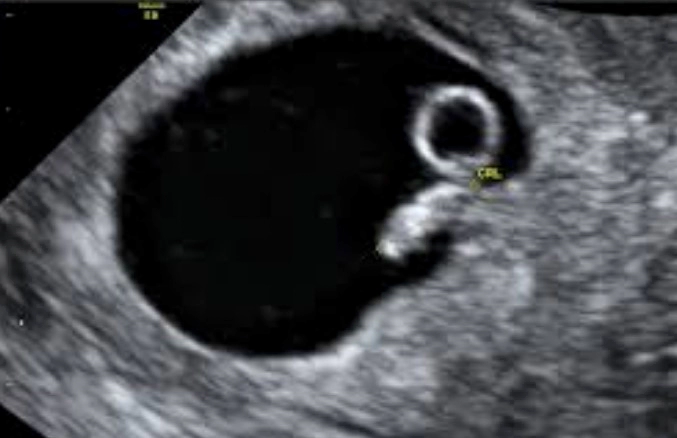

초음파

임신 6주차에는 초음파를 통해 태아의 심장 박동을 확인할 수 있습니다. 초음파는 또한 태아의 위치와 성장을 확인하는 데 사용됩니다.